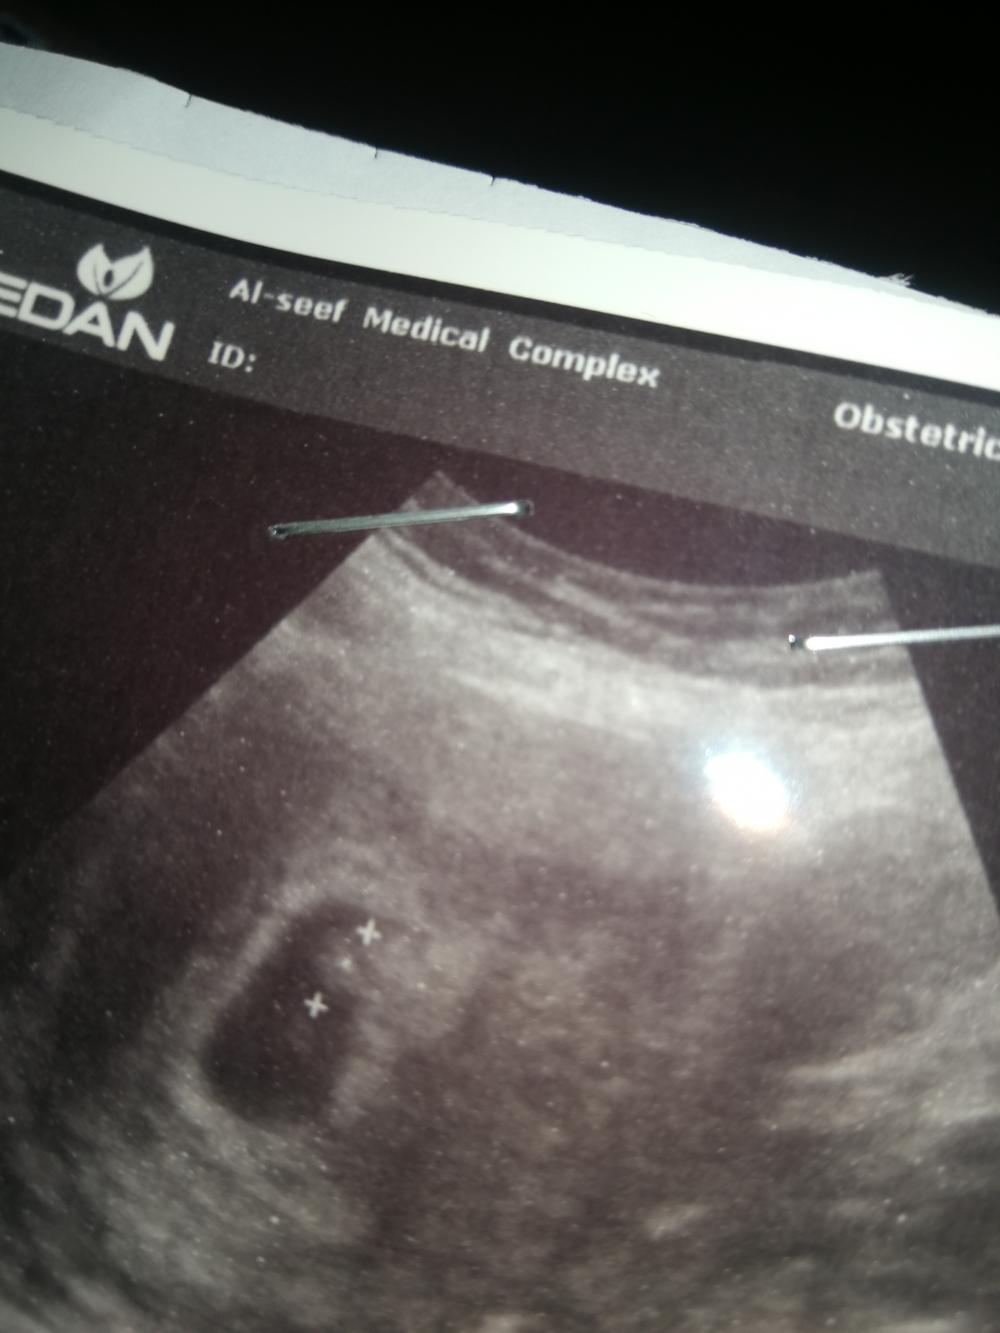

ذا سوناري خمنوووو لي انا خمنت بشوف ترى نفس تخمينكم والالا😁

توه ظهرت ماعرفت شي مو واضح

هذا سونار فالاسبوع السابع

بحلقوا عيونكم شوفوا هل تشوفون البيبي متشكل مثل الربيانه او قريب منها

ولا تشوفونه قطعه

نحن ترا نخمن لبعض عن طريقه نظرية الناب والجمجمه ومو شرط صح مجرد تخمينات